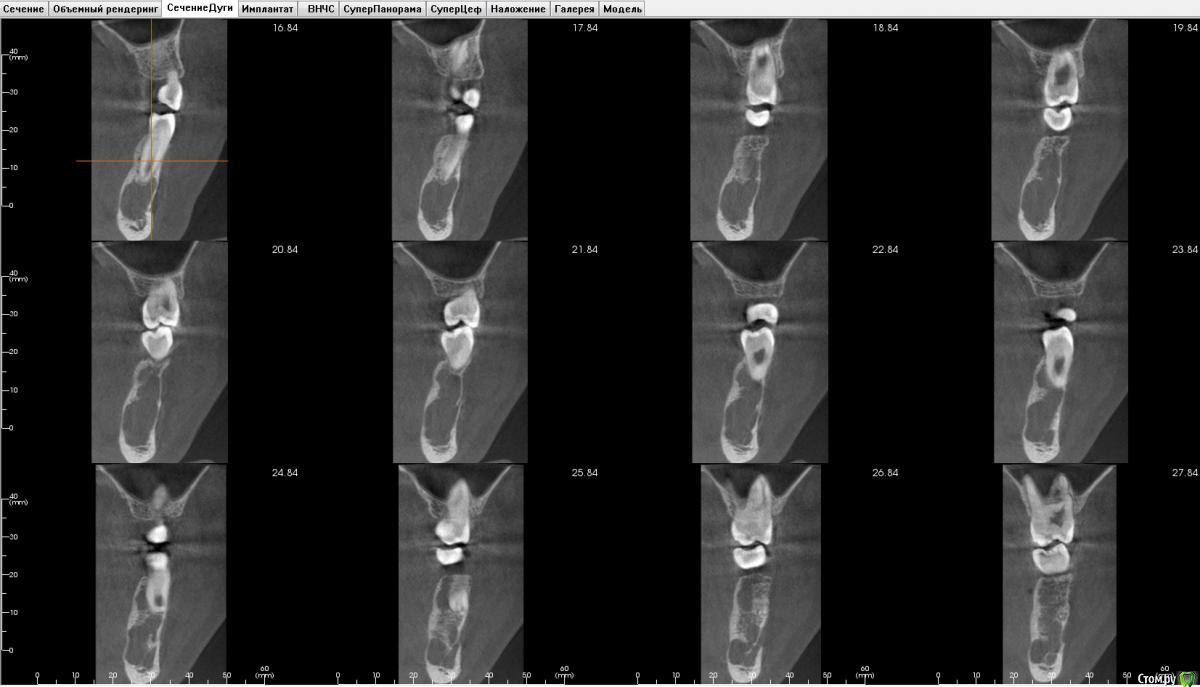

bullbull Опубликовано 17 ноября, 2015 Поделиться Опубликовано 17 ноября, 2015 При ОПТГ и последующей КТ обнаружена полость в кости с мягкотканным содержимым (300-400 HU). Клинических проявлений никаких. Пациентка 13 лет, планируется постановка брекетов.Что это может быть? Может стоит направить в ЧЛХ? Ссылка на комментарий

hemchik Опубликовано 17 ноября, 2015 Поделиться Опубликовано 17 ноября, 2015 Вроде там есть камерность , что характерно для амелобластомы. Если есть подозрение на опухоль нужно делать пункцию. Ссылка на комментарий

девять Опубликовано 23 ноября, 2015 Поделиться Опубликовано 23 ноября, 2015 Тень проецируется в области выхода 3-ей ветви, если бы было новообразование были бы явления сдавления нерва.По снимку муфтообразного утолщения нет.Нет ли гемангиом на лице.Наверно отправить на консультацию в члх. Ссылка на комментарий

bullbull Опубликовано 25 ноября, 2015 Автор Поделиться Опубликовано 25 ноября, 2015 Лицо не изменено, клинических проявлений ни со стороны зубов, ни со стороны лица нет.От консультации у ЧЛХ отказались. Без консультации мы, в свою очередь, отказались устанавливать брекеты. Ссылка на комментарий